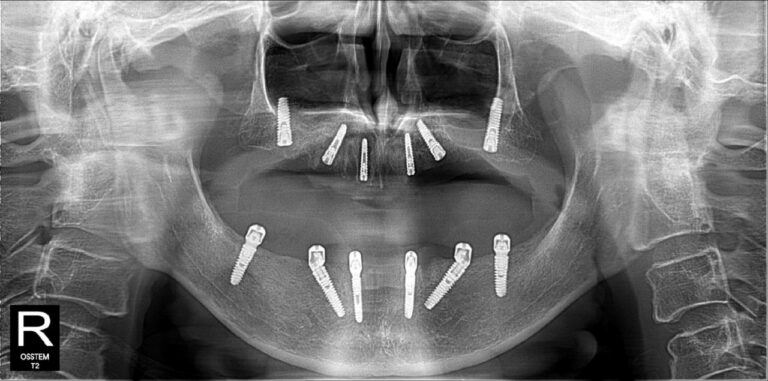

Không nằm ở lời nói mà thể hiện qua kết quả điều trị thực tế. Những hình ảnh X-quang dưới đây là sự khẳng định cho năng lực phẫu thuật và sự chính xác tuyệt đối của BS CKI Nguyễn Trung Khánh trong các ca đại phẫu thuật Implant nhiều lần cắm.